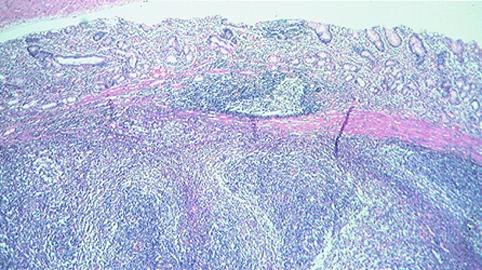

疾病(病理主体)的分类恶性淋巴系肿瘤/恶性淋巴瘤

检查方法病理切片(微观)

肿瘤的深度sm